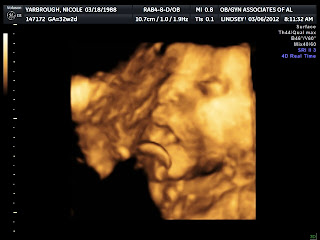

I am now 35 weeks and SO ready to not be pregnant anymore! Don't get me wrong, I have enjoyed this experience of feeling my baby moving and knowing that I am keeping him safe and sound, but I am SO over it. I'm ready to hold him and play with him. I am giving him 2 more weeks to keep growing and "baking", but then I will be hoping every day that he will come asap! I have been having a lot of what I think are Braxton Hicks contractions. My belly gets so tight and rock hard. I swear my belly is rock solid more than it is soft these days. They don't hurt, but it's so uncomfortable, especially when trying to eat or riding in the car. I still feel Jonah moving a lot, but it's changed to a slower rolling kind of movement, instead of kicking and jabbing, which I have to say I'm thankful for. I'm just so ready to see my Derek Brandon looking thing :)